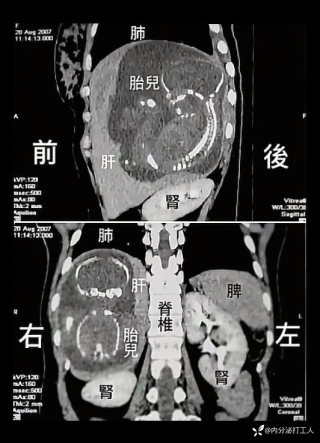

一例罕见宫外孕

病例信息转载一例影像,请各位老师检阅